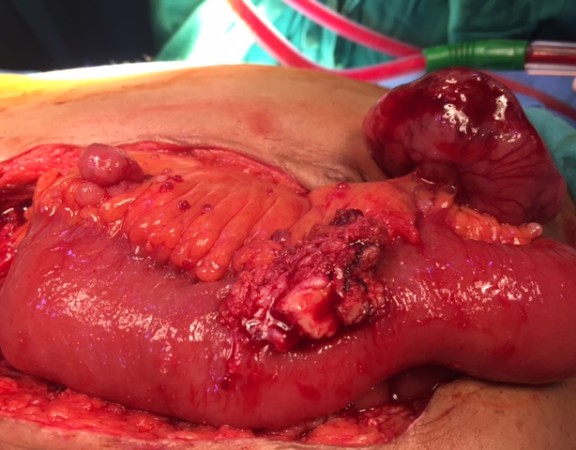

A 57 year old male was diagnosed as a case of gastrointestinal stromal tumor (GIST) 4 years ago and had undergone surgery for the same. The […]

A 57 year old male was diagnosed as a case of gastrointestinal stromal tumor (GIST) 4 years ago and had undergone surgery for the same. The […]